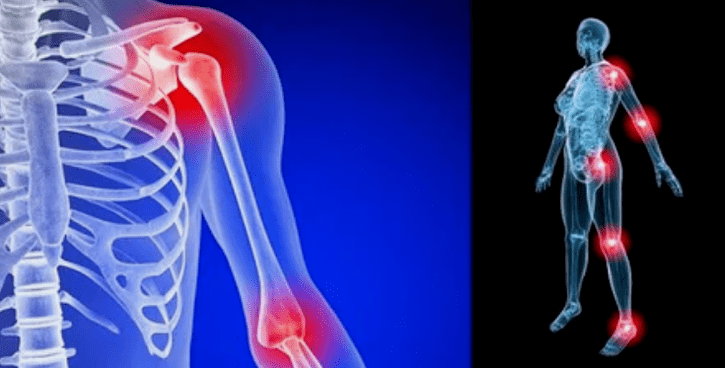

Die Manifestationen der Krankheit unterscheiden sich in Abhängigkeit von der Lage wenig, die Anzeichen spiegeln aufgrund von hoher Belastung häufiger auf Knie, Schultern und Hüftfugen wider.

- Rötung der Rötung. Es befindet sich in der Nähe des Krankengelenks. Dies weist auf einen entzündlichen Prozess und ein Fortschreiten der Krankheit hin. Der Arzt versteht, dass die Synovialbedeckung betroffen ist. Dies führt zu der Ansammlung von Flüssigkeiten und erhöhten Schmerzen.